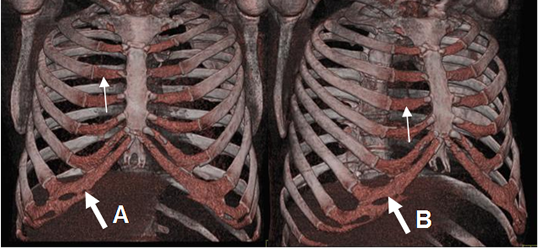

En la parte anterior, las costillas se clasifican en: (1). (Fig 1 y 2).

Fig 1. Costillas normales.

A y B: TAC reconstrucción 3D. Costillas verdaderas que se unen directamente al esternón (Flechas delgadas) y falsas cuyos cartílagos se fusionan. (Flechas gruesas).

Fig 2. Costillas normales.

TAC reconstrucción 3D. Costillas flotantes, que no se unen al esternón.